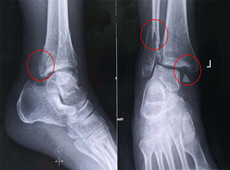

【醫(yī)療科普】踝關節(jié)骨折的主要類型及其影像學表現(xiàn)

大家好,我是南京醫(yī)科大學第二附屬醫(yī)院骨科副主任醫(yī)師王伯堯,從事骨科臨床工作十余年,擁有豐富的骨科臨床經(jīng)驗,主要研究方向為骨科手術機器人的開發(fā)與臨床應用,今天跟大家介紹踝關節(jié)骨折的幾種常見類型及其在X影像上的表現(xiàn)。接下來跟...